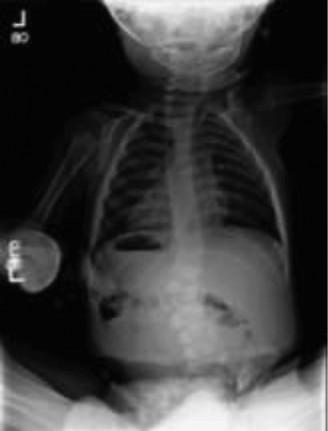

Advanced Imaging and Diagnostics

The initial radiographic evaluation of the swollen thigh will confirm the presence of a femur fracture. However, the diagnostic workup for a non-ambulatory infant with a suspicious fracture must immediately pivot to a systemic evaluation for occult injuries. The historical practice of ordering a "babygram"—a single, large-cassette radiograph encompassing the entire infant—is obsolete, medically unacceptable, and medicolegally indefensible. A babygram suffers from severe parallax distortion, inadequate penetration of thicker body parts, and over-penetration of thinner parts, rendering it useless for detecting subtle, high-specificity fractures.

The Skeletal Survey Protocol

The gold standard diagnostic imaging modality is a formal, high-detail Skeletal Survey, performed according to the rigorous guidelines established by the American College of Radiology (ACR) and the American Academy of Pediatrics (AAP). This survey consists of 21 distinct, tightly collimated radiographic views, including bilateral AP and lateral views of the skull, AP and lateral views of the axial skeleton (cervical, thoracic, and lumbar spine), AP views of the bilateral humeri, forearms, femurs, and lower legs, as well as specific views of the hands, feet, and pelvis.

We are specifically hunting for fractures that carry a high specificity for child abuse. These include the Classic Metaphyseal Lesions (CMLs), posterior rib fractures (caused by the clinician's or abuser's hands squeezing the infant's thorax, levering the ribs over the transverse processes), scapular fractures, spinous process fractures, and sternal fractures. Furthermore, the skeletal survey allows us to identify fractures in various stages of healing. Finding a fresh, acute femur fracture alongside a healing posterior rib fracture with robust callus formation proves that the child has been subjected to multiple traumatic events over time, cementing the diagnosis of NAT.

- The Pitfall of the "Babygram": Never order or accept a babygram. Insist on a formal, 21-view Skeletal Survey per ACR guidelines. Missing an occult CML or rib fracture because of poor imaging technique is a catastrophic diagnostic error.